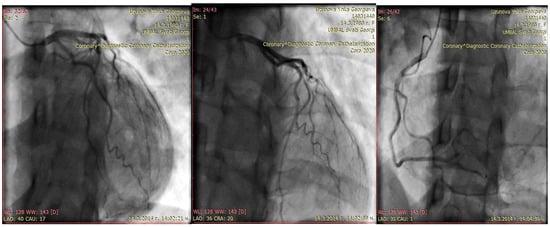

| first month | 1. no cardiac sighs 2. EchoC-normal EF, but persist regional apical wall motion abnormalitica 3. coronary angiography—normal 4. Initially diagnosis—perypartal cardiomyopathy 5. treatment with torasemide 5 mg, carvedilol 2 × 3.125 mg, and ramipril 2.5 mg |